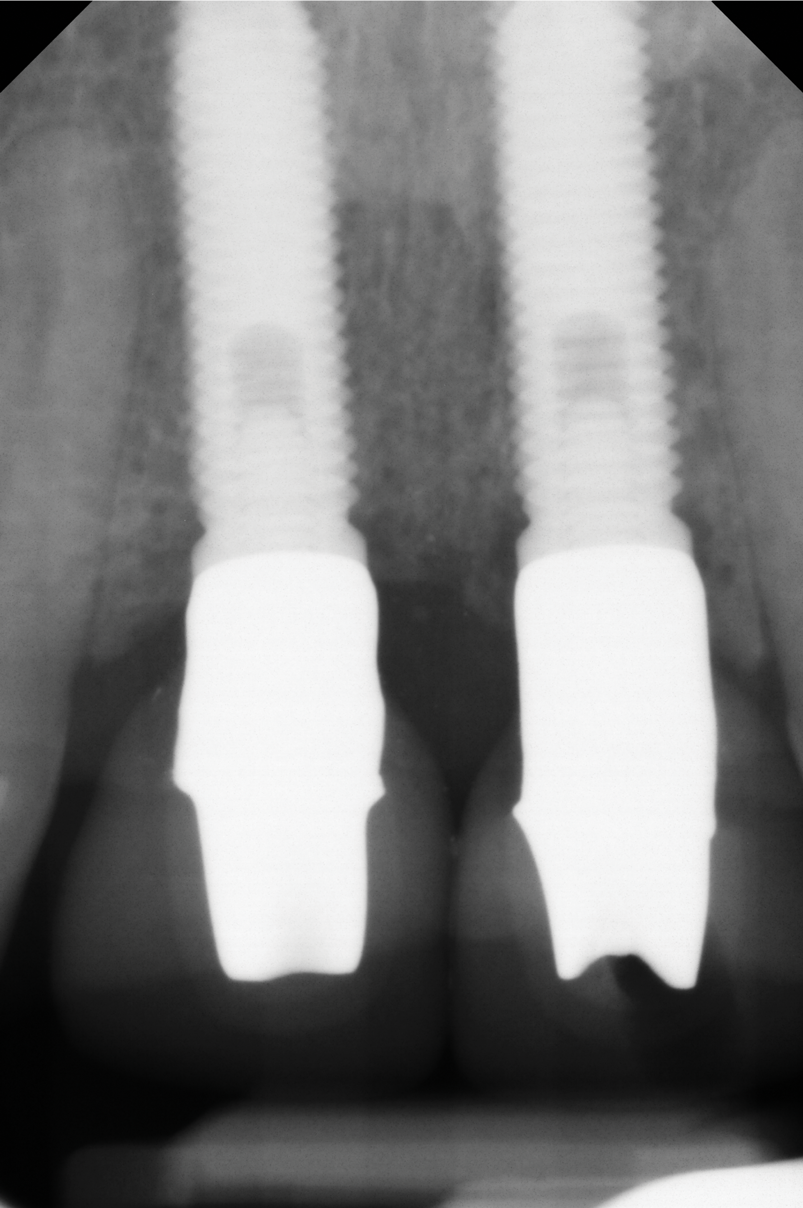

Fig 2. Baseline periapical x-ray.

Figure 2

A 46-year-old systemically and periodontally healthy woman presented to the Graduate Periodontics Clinic at the University of Michigan School of Dentistry with the chief complaint of poor esthetics of her smile due to two dental implants (Nos. 8 and 9) showing their metal components (Figure 1). The patient reported that the implants had been placed 15 to 20 years previously after an accident. Clinical examination revealed that the implants had probing depths within 3 mm (facial probing depth of 3-2-3 mm for implant No. 8 and 2-2-2 mm for implant No. 9), no bleeding on probing, and no suppuration; the implants were therefore diagnosed as healthy (Figure 1 and Figure 2). The papilla between the two implants was deficient on the buccal aspect. The implants were buccally positioned, and a substantial lack of soft-tissue volume was noted.

Figure 14 depicts the final outcome at 1 year (which can be compared to the pretreatment photograph in Figure 1). Figure 15 through Figure 18 show clinical comparisons of the outcome at baseline and 1 year, while Figure 19 and Figure 20 provide an ultrasonographic characterization of the soft tissue at baseline and 1 year. The facial probing depths at 1 year were 3-3-3 mm for implant No. 8 and 3-2-3 mm for implant No. 9. The patient was highly satisfied with the esthetic outcomes and overall treatment.